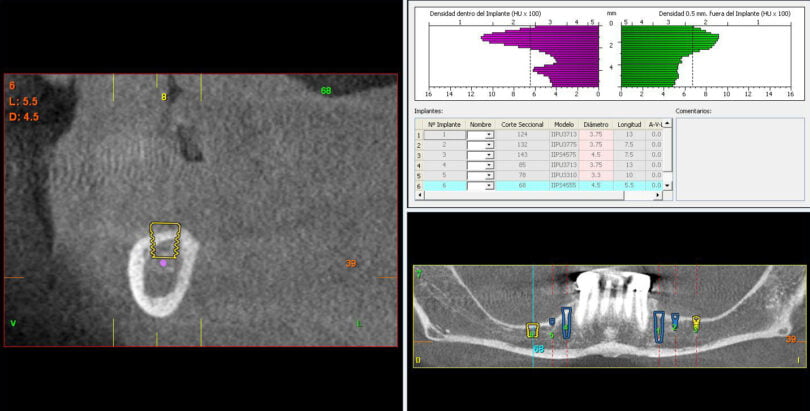

Quatro dos seis implantes foram de 5,5 mm de comprimento por 5 mm de diâmetro, um implante foi de 6,5 mm de comprimento por 3,75 mm de diâmetro e o último implante foi de 6,5 mm de comprimento por 5 mm de diâmetro (figura 2).

As seguintes imagens apresentam um dos casos incluídos no estudo (figura 03 – 15).